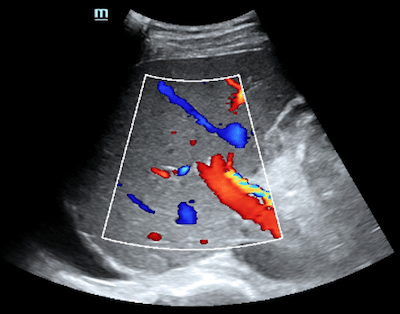

Medical professionals frequently use this imaging examination to detect ailments, including cirrhosis, fatty liver disease, and liver tumors. Furthermore, it can effectively uncover any irregularities within the bile ducts and blood vessels that serve the liver.

In conjunction with blood tests, shear wave elastography is used to determine the staging and progression of liver fibrosis with good sensitivity and repeatability. It is an adjunct to conventional 2D ultrasound exams, aiding in initial characterization and treatment follow-up.

An ultrasound is a safe and effective diagnostic test that provides detailed images of the liver’s internal structures. It is a non-invasive procedure that does not use ionizing radiation and can detect liver disease, tumors, and abnormalities in the bile ducts and blood vessels. Liver ultrasound is an excellent diagnostic tool to help detect, evaluate, and diagnose liver disease.